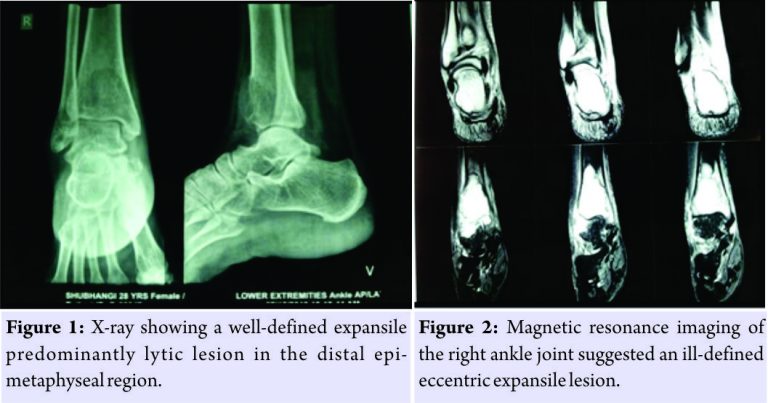

A 28-year-old female presented to us in July 2015 with complaints of pain and restricted movement of the right ankle joint since 1 month. The pain aggravated on walking. There was no history of trauma and was not associated with fever, loss of weight, or any other constitutional symptoms. History and family history were non-contributory. Clinical examination revealed no inspectory findings. Palpation revealed tenderness over the anterior aspect of the distal tibia with no local rise of temperature. Range of motion of the right ankle joint was painful and restricted. X-rays revealed a well-defined expansile predominantly lytic lesion in the distal epi-metaphyseal region of the right tibia with minimal periosteal reaction seen along the medial margin suggestive of malignant tumor of the bone (Fig. 1). Magnetic resonance imaging (MRI) of the right ankle joint suggested an ill-defined eccentric expansile lesion measuring 4.3 (CC) × 3.0 (transverse) × 2.9 (anteroposterior) involving epi-metaphyseal end of the lower end of tibia causing cortical breach and having extra-osseous tissue component with the abnormal signal in flexor and extensor group of muscles with the possibility of GCT (Fig. 2).